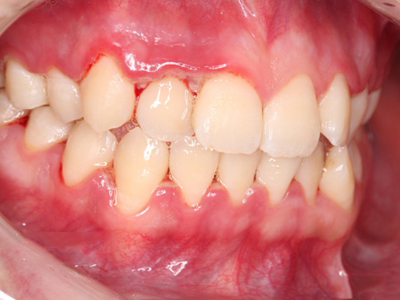

急性坏死性溃疡性龈炎症状图片

急性坏死性溃疡性龈炎起病急,病程短,常为数天至1-2周,以龈乳头和龈缘的坏死为其特征性损害,尤以下前牙多见,初起时龈乳头充血水肿,个别龈乳头顶端可发生坏死性溃疡,上覆有灰白色坏死物,中央凹下如火山口状。龈缘如虫蚀状,坏死区出现灰褐色假膜,擦去后可见出血创面。龈乳头被破坏后与龈缘成一直线,如刀切状。病损一般不波及附着龈,患处牙龈极易出血,疼痛明显并有腐败性口臭。

重症患者可有低热、疲乏等全身症状,并可伴有下颌下淋巴结肿大和压痛。有的患者可能进展为坏死性龈口炎、坏死性溃疡性牙周炎等疾病,从而导致牙周袋形成、牙槽骨吸收和牙齿松动。